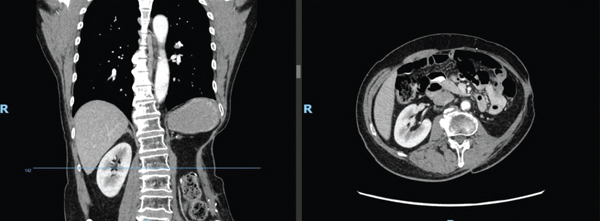

A 62-year-old Malay gentleman with hypertension, hyperlipidemia, and ischemic heart disease presented to our service with a 6-month history of a left upper back lump associated with loss of weight. Preoperative magnetic resonance imaging (MRI) showed an aggressive, infiltrative soft tissue tumour with involvement of the spleen, left kidney, pancreas, descending colon, ribs, and paravertebral muscles. Considerations included a primary aggressive sarcomatous tumour, lymphoma, or large metastatic deposit. The computer tomography (CT) scan of the thorax, abdomen, and pelvis of the patient is shown in Figure 1. It depicts an ill-defined mass in the left retroperitoneum and paracolic gutter, extending beyond the left posterior abdominal wall, measuring 15.5 cm by 12.3 cm. There were no distant metastases.